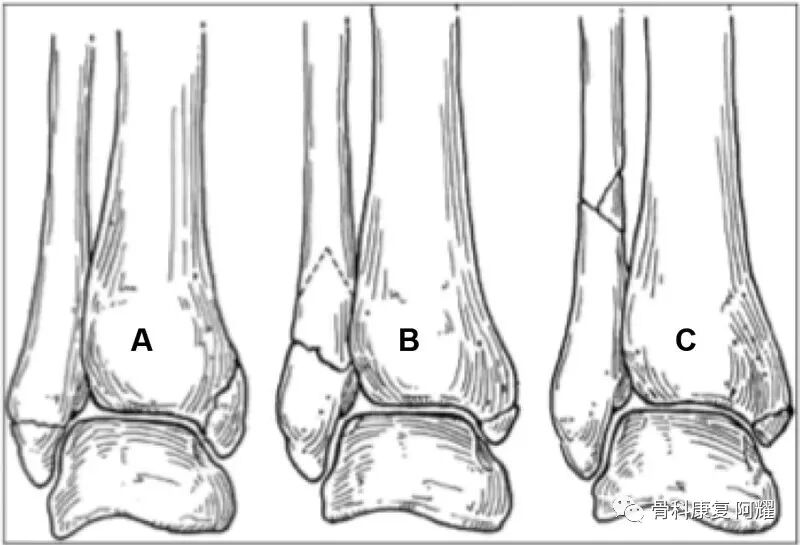

2.Danis-Weber 分型

通过腓骨骨折高度与下胫腓联合间的位置关系进行命名的分型方法。因为分型方法简单,因此在医生间容易达成共识。Danis-Weber分型是根据腓骨骨折位置与踝关节的高度进行分型。分为A型(38%)、B型(52%)、C型(10%)。

Danis-Weber分类A. A型骨折;B. B型骨折;C. C型骨折